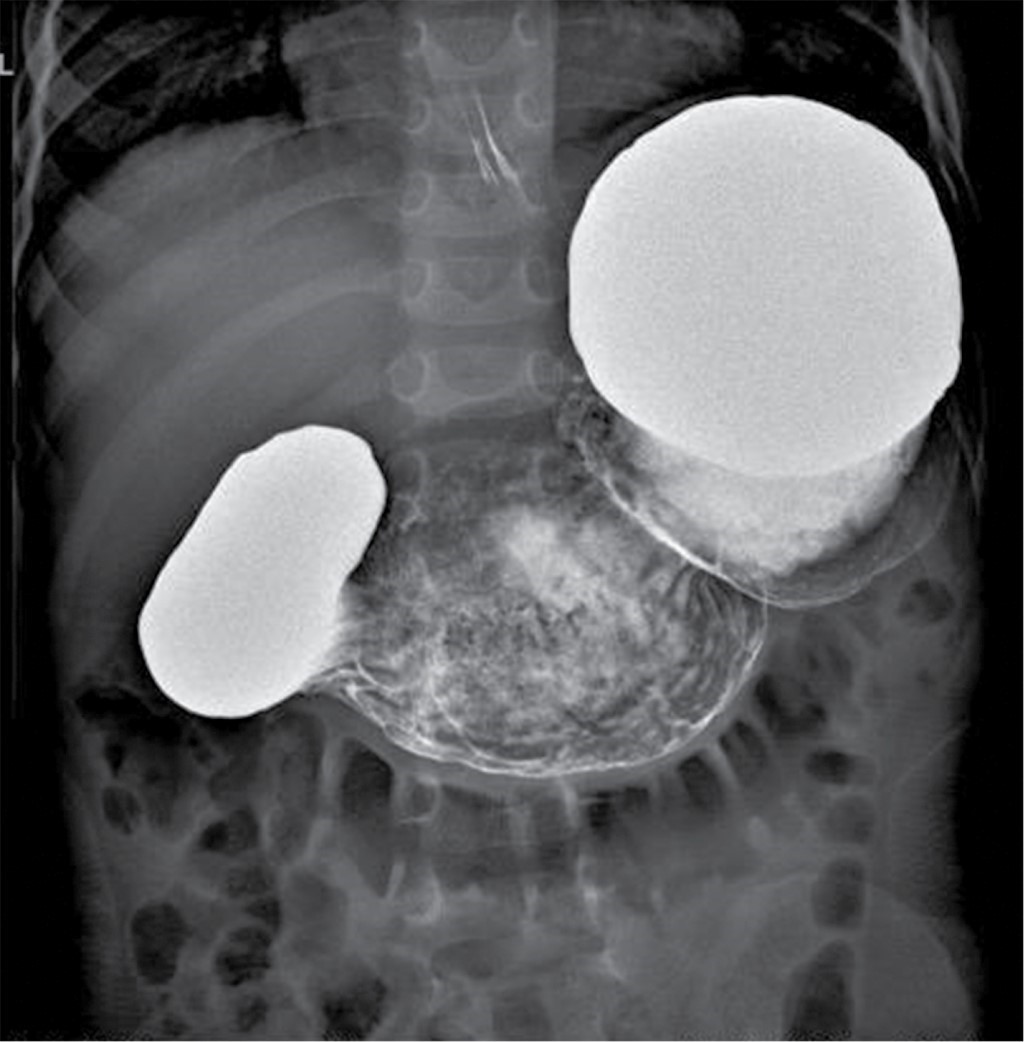

Figure 3